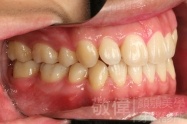

變臉矯正,原來戽斗妹跟大歪臉變成自信正妹

經由本院3D數影X光影像儀分析、與3D齒顎顏矯正技術,再配合口腔顎面正顎專科醫師施以正顎手術治療,雙方共同合作,使患者臉部外觀有很好的改善,大歪變小歪,產生了天南地北的大改變,她的人生也整個變得不一樣。

因為矯正與正顎手術的配合,使「戽斗妹」變成了「陽光正妹」,完全的改變了她的人生,在面對各種場合、與人交際都散發出自信微笑。所以,奉勸家長,如果小朋友有臉顎畸型的問題,應該考慮配合做這種簡單、安全、有效的正顎手術。

「3D齒顎顏矯正」,不止矯正您的牙齒,也會改變您的人生。「治療前」和「治療後」出社會的人生際遇一定會截然不同。